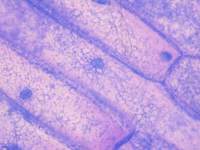

人卵巢癌组织源细胞细胞图片: